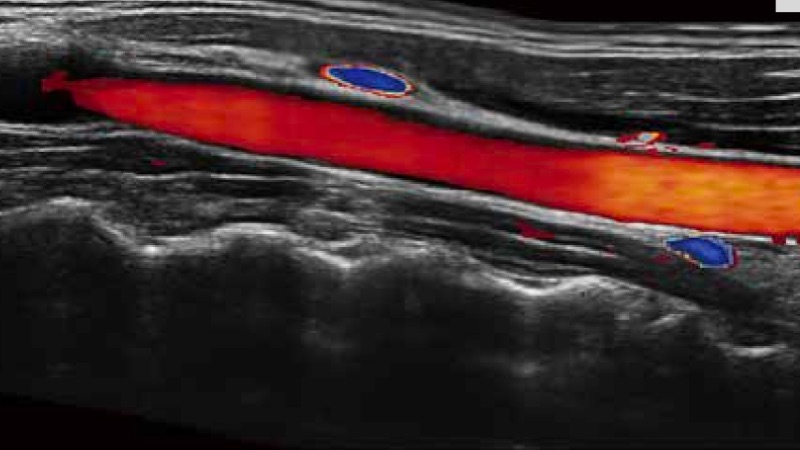

開立醫(yī)療通過不斷的技術(shù)創(chuàng)新,為大眾的生命健康提供持續(xù)關(guān)愛。P12 Plus采用全新一代超聲成像平臺,新平臺旨在將真實(shí)還原組織解剖結(jié)構(gòu)作為首要目標(biāo)。平臺采用全新集成化硬件模塊,搭載新一代芯片,系統(tǒng)性能得到大幅提升,為您的診斷提供了豐富的臨床信息。優(yōu)異的圖像表現(xiàn),豐富的探頭配置,全面的應(yīng)用功能,為您日常診斷提供了可靠的助手。

P12 Plus

彩色多普勒超聲診斷系統(tǒng)